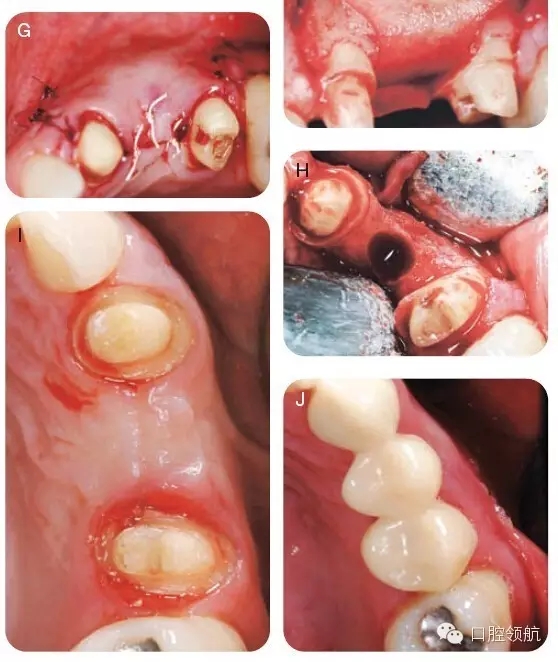

用2%利多卡因(1/100000腎上腺素)行下牙槽后、中神經(jīng),腭大神經(jīng)阻滯麻醉,局部浸潤麻醉。附加兩個垂直方向的松弛切口使得視野更加清晰并減低術(shù)后瓣撕裂的可能,上頜右側(cè)1/4區(qū)域翻開全厚瓣以充分暴露骨皮質(zhì)(圖6A~C)。暴露術(shù)區(qū),用圓形金剛鉆去除該區(qū)的骨皮質(zhì),使得術(shù)區(qū)有血液流出。打入兩個10mm的支帳螺絲并且確認(rèn)其穩(wěn)定(圖6D)。取稍過量的脫礦凍干骨置于該區(qū)域(圖6E)。放置堅固的可吸收膠原膜( O s s e o g u a r d -Collagen Matrix, Inc, Franklin Lakes,NJ, USA)于移植物上(圖6F),復(fù)位瓣并原位縫合。組織愈合良好(圖6G)。在GBR術(shù)后6個月,再次麻醉并暴露術(shù)區(qū),制備直徑為4.1mm的植入位點,使得頰舌側(cè)有足夠的余留骨,以確保組織的長期穩(wěn)定性并防止組織退縮(圖6H),在最終固定冠修復(fù)前,拍攝照片,顯示牙槽骨寬度顯著改善(圖6I,J),圖7為最終修復(fù)當(dāng)日照片。

圖6 (A~J)手術(shù)時的口內(nèi)照。